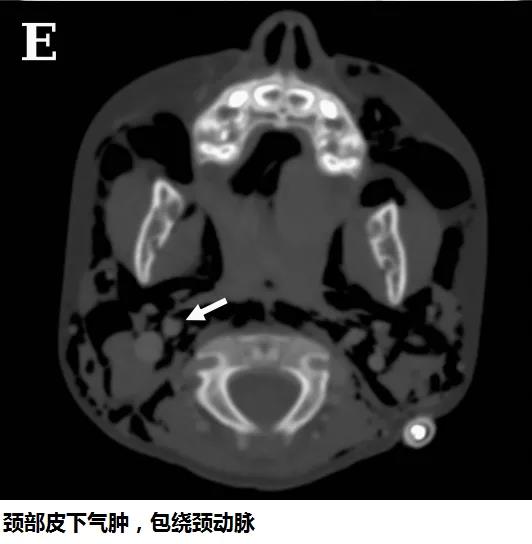

頭顱、胸部CT提示廣泛皮下氣腫、縱隔氣腫、心包積氣、甚至眼眶周圍都積氣,眼球突出!頸部無感染征象,腸管無破裂征象,看來氣體還是來自肺部。但是,肺部無感染、無肺大泡、無劇烈咳嗽,只有間質性肺氣腫。縱隔氣腫、皮下氣腫的治療,核心是根除病因,切開引流效果不像氣胸那么理想,而且縱隔切開引流還存在手術風險。找不到病因,如何是好?考慮患者是過敏體質,有皮疹,繼續呼吸機輔助呼吸,先治療過敏,肌肉注射腎上腺素、靜脈注射類固醇激素和抗組胺藥、吸入支氣管擴張劑等。經上述治療,臨床表現和影像學方面都有迅速的改善。隨后拔出氣管導管,口服類固醇激素出院,門診隨訪。